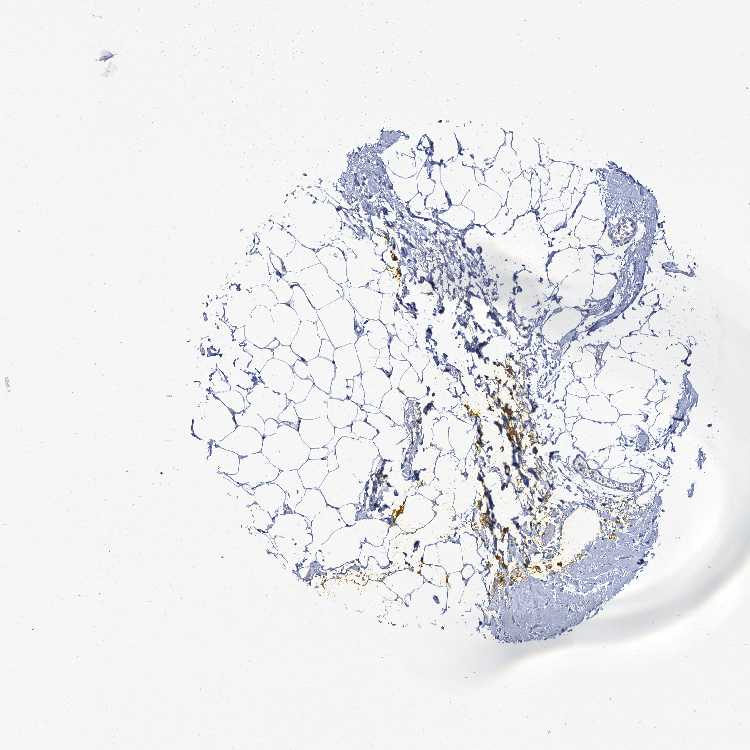

SOFT TISSUE 2 - Antibody stainingi

Antibody staining in the annotated cell types in the current human tissue is reported as not detected, low, medium, or high, based on conventional immunohistochemistry profiling in selected tissues. This score is based on the combination of the staining intensity and fraction of stained cells.

Each image is clickable and will lead to virtual microscopy that enables deeper exploration of all samples and also displays staining intensity scores, fraction scores and subcellular localization as well as patient and tissue information for each sample.

Antibody HPA039117

Chondrocytes Not detected

Fibroblasts Not detected